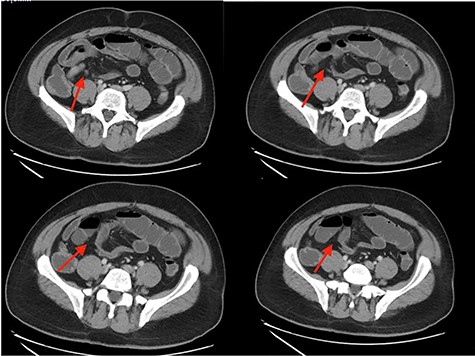

This case is a 54-year-old-male with past medical history of obesity, laparoscopic cholecystectomy, recurrent small bowel obstructions in 1997 and 2006 resolved with supportive care and COVID-19 infection in December 2020 who presented to the Emergency Department with nausea, non-bilious vomiting, non-bloody diarrhea and progressively worsening, sharp, diffuse abdominal pain for 1 week. On physical examination, he had diffuse abdominal tenderness. His white blood cell count was 3.8, consistent with his recent COVID-19 infection. Abdominal CT showed partial small bowel obstruction with a transition point in the right lower quadrant as well as fluid in the colon and throughout the bowel (Fig. 1). The patient had two episodes of bilious emesis overnight after his admission. A nasogastric tube was inserted and conservative management was attempted. The patient had persistently worsening abdominal pain, and was taken to the operating room for an exploratory laparotomy 2 days after admission.

CT abdomen/pelvis showing SBO with transition point in right lower quadrant.